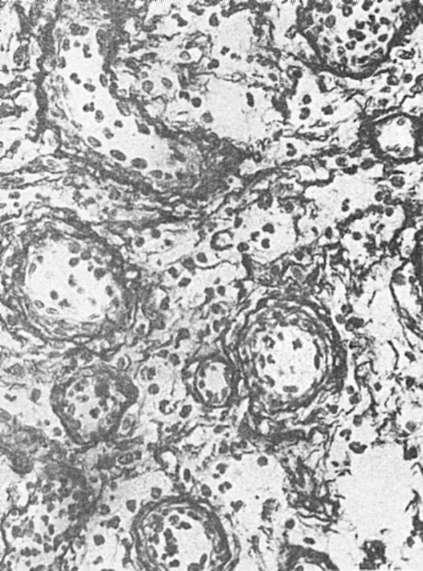

Рис. 83. Грануляционная ткань. Между тонкостенными сосудами много недифференцированных клеток соединительной ткани и аргирофильных волокон. Импрегнация серебром